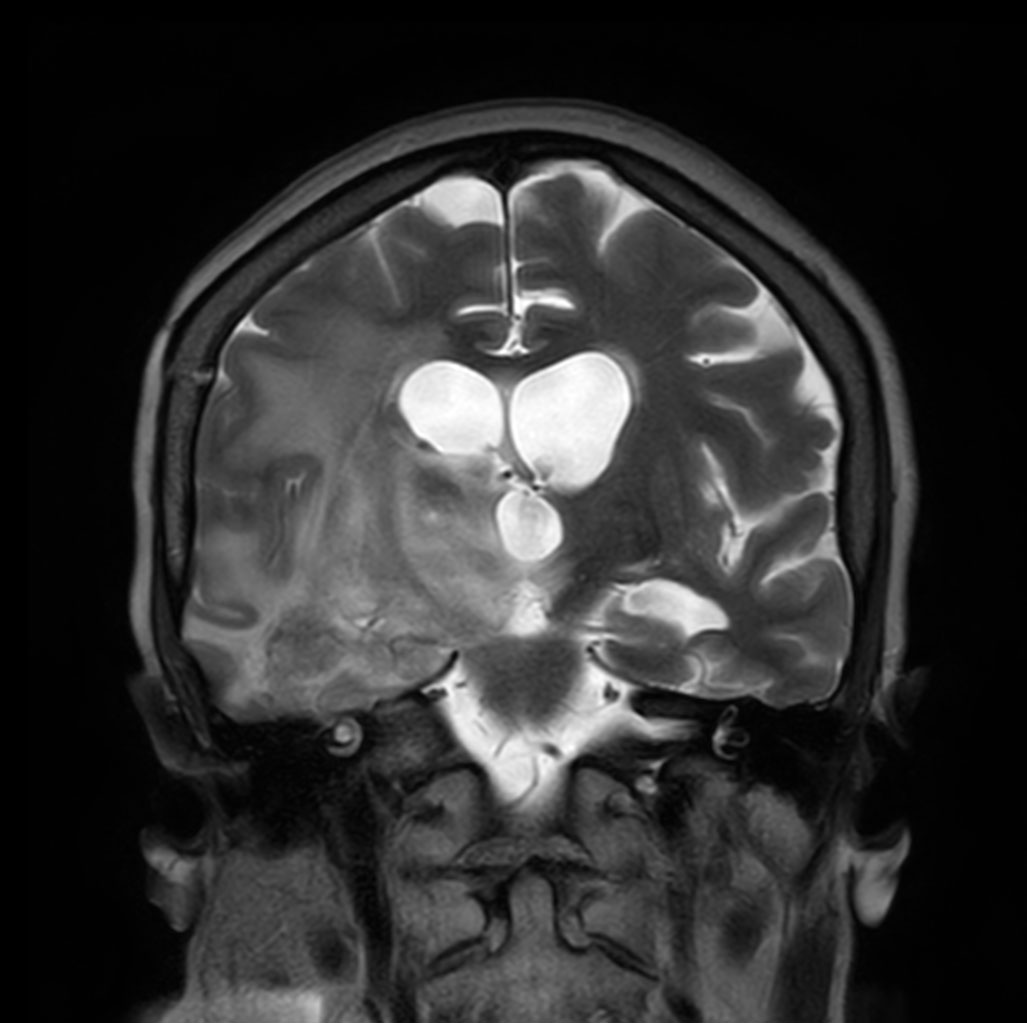

Coronal T2w TSE

-